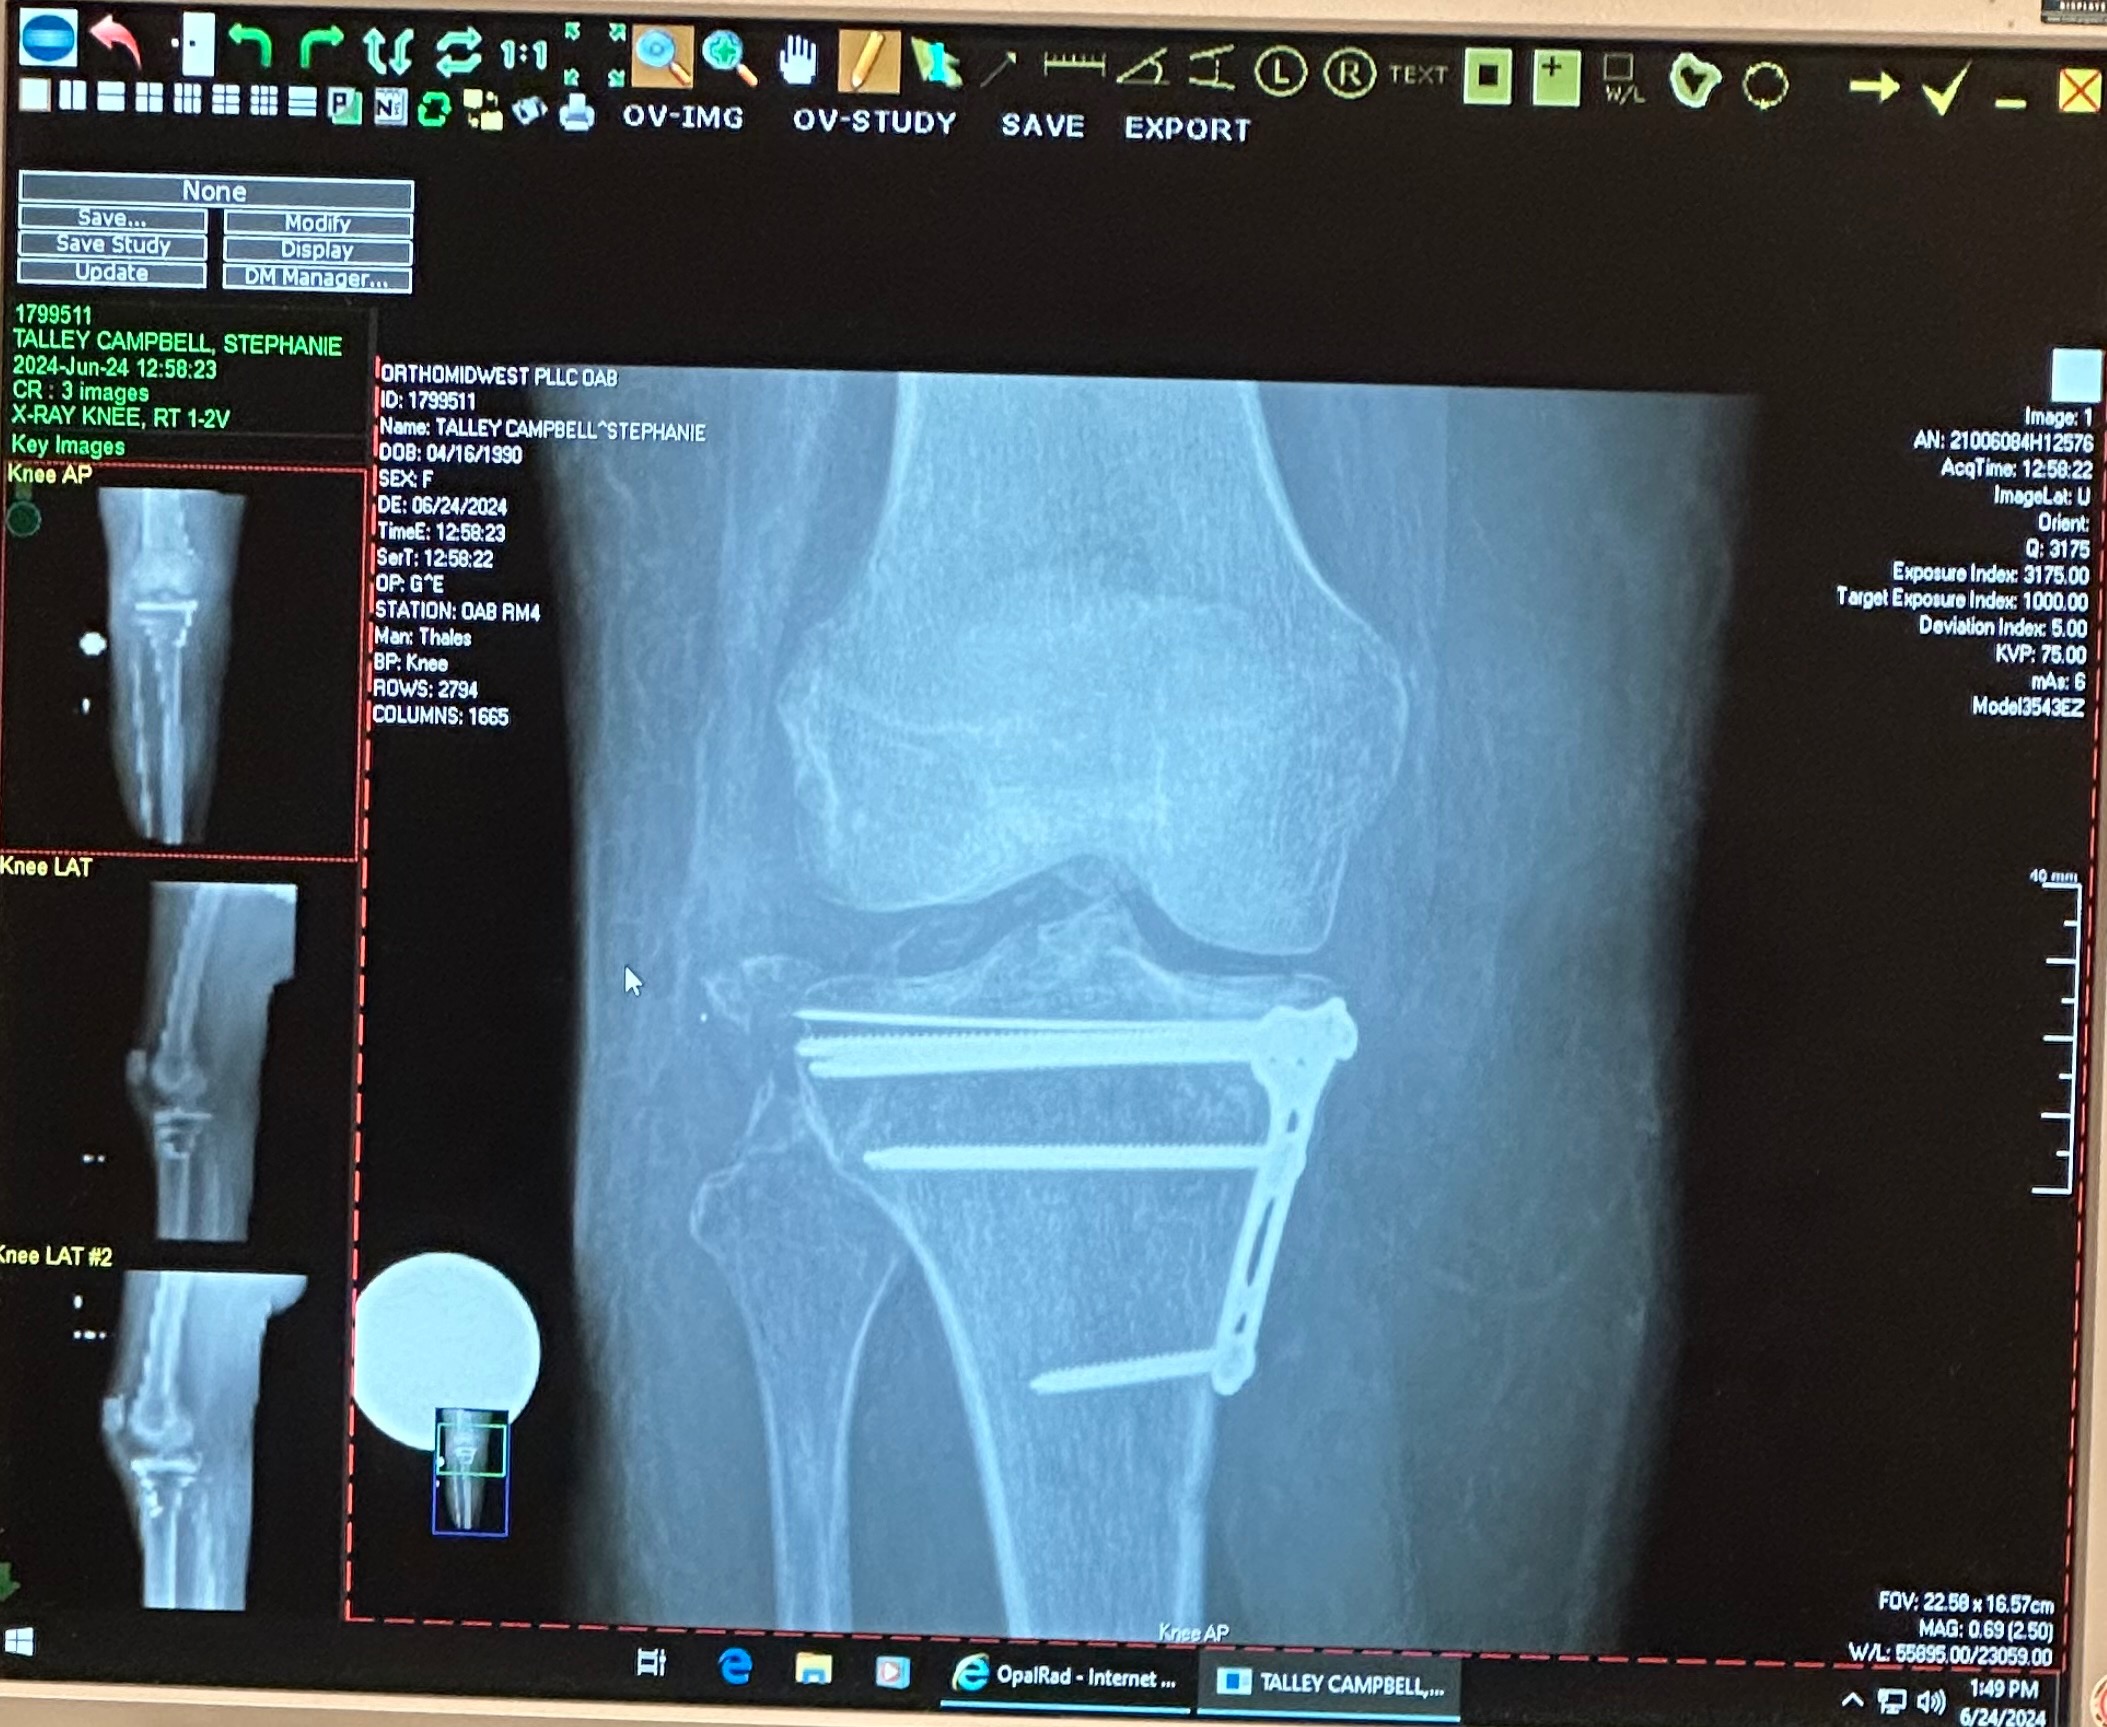

Hello! My name is Stephanie and I’m here posting on behalf of myself and my husband. Not many people know, but I’ve been out of work for almost a year due to breaking my tibia plateau in multiple pieces, tearing all of the ligaments in my leg, and having nerve damage to my foot in March of 2024. Due to the severity of my injury, this has financially put a huge burden on our household. I have been unable to return to work because I’m a server and it is an unsafe environment for me considering I still at this time have stability issues. We are literally drowning in bills and paycheck to paycheck, on one person's income, is not even touching the tip of the iceberg. I am here, last resorting to this page to attempt to put us back on our feet again. Any little bit would help, even if it’s just a dollar. ❤️ Thank you!

Today I got news that I might potentially be having surgery again. The outlook was not what I was hoping for, but it’s probably my best option moving forward. Recovery looks like another long process, and there’s not much more we can do but accept the outcomes ahead of us. I’m just trying to stay hopeful that I make the right decision moving forward for my long term health.